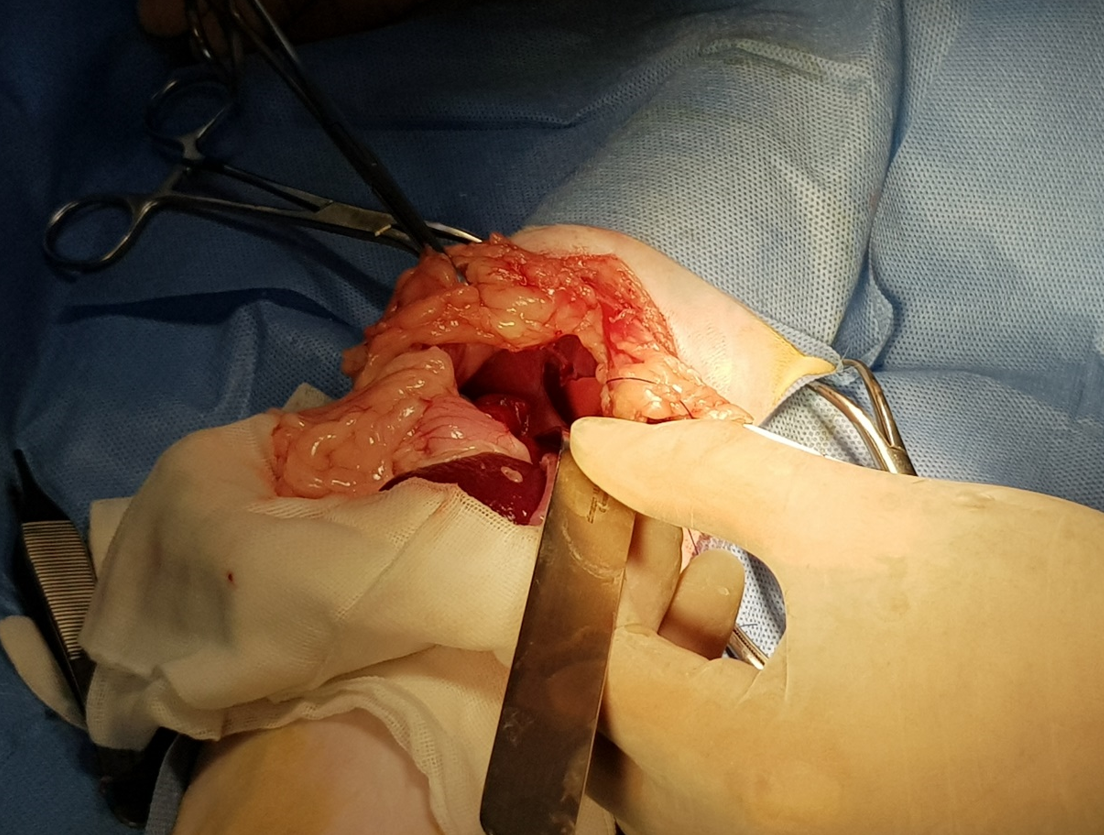

手術過程

開腹後發現肝臟從腹腔掉到胸腔內,橫膈破了一個大洞

將橫膈修補起來,看到破洞縮小很多

看到橫膈膜全貌

將胸腔內的空氣抽掉讓肺臟可以正常的擴張